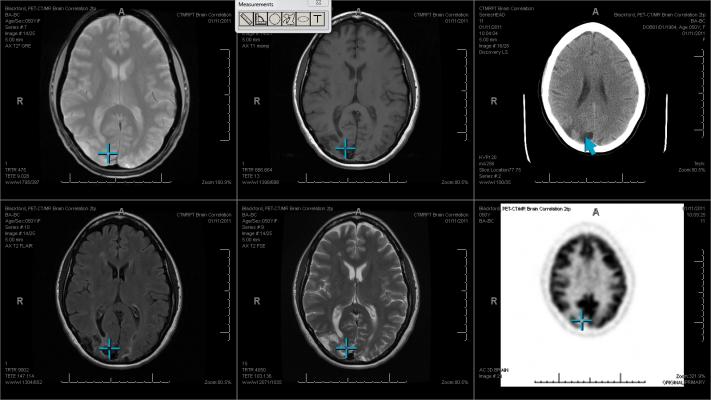

The Blackford platform provides centralized deployment and management of image processing products across the healthcare enterprise. It provides access to Blackford’s automated image registration and enables a wide range of automated processing solutions from Blackford and its Alliance Partners to be quickly deployed through any PACS or image viewer.

eRAD will initially deploy Blackford’s Smart Localizer product at RadNet centers, but the Blackford platform can also be used to quickly and easily roll out additional Alliance Partner products in the future.

“We are rolling out the Blackford platform to immediately enhance our RadNet clinics with the automatic image registration capabilities of Smart Localizer, but we are also very excited by the potential to deploy other new technologies,” said Ranjan Jayanathan, general manager of eRAD and CIO of RadNet. “Blackford provides a single platform to simplify the implementation and management of multiple AI and intelligent image processing modules, with a centralized access point for training, support and monitoring of the overall solution.”